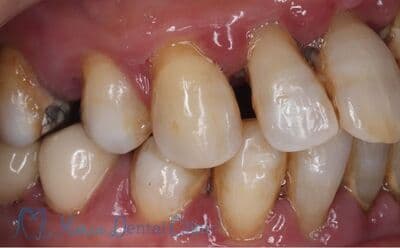

重度の歯周病

歯周病によって骨の喪失が著しく、歯が縦に揺れている状態。